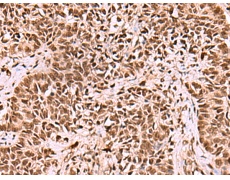

IHC positive control: |

Human ovarian cancer and Human thyroid cancer |

IHC Recommend dilution: |

70-350 |